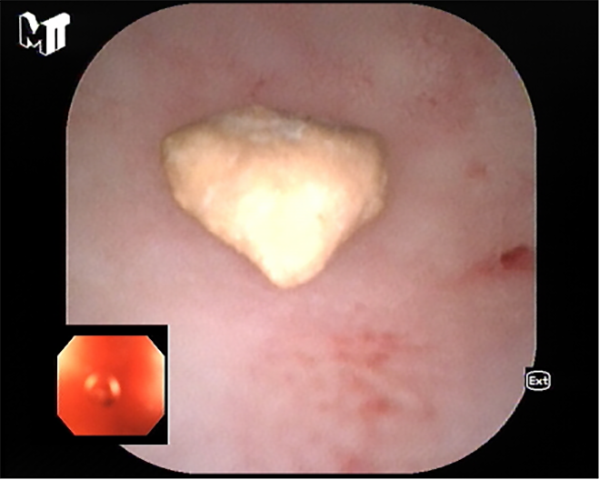

患者李某因慢性腹痛、腹瀉來消化內(nei)科(ke)就診,在(zai)腸鏡檢(jian)查過(guo)程(cheng)中(zhong)髮(fa)現(xian)患者闌尾開口處明顯腫脹、充血,并有(yǒu)白色膿液排(pai)出,進(jin)一(yi)步完善(shan)腹部(bu)CT後(hou)明确診斷(duan)闌尾炎、闌尾糞石嵌頓。征得患者同意後(hou),在(zai)邸雅南(nan)主(zhu)任的(de)帶領(ling)下,張波(bo)副主(zhu)任咊(he)康奎、青勝(sheng)醫(yī)生(sheng)等(deng)團(tuán)隊(duì)成(cheng)員(yuan)通(tong)過(guo)腸鏡活檢(jian)孔道送入“洞察”子(zi)鏡(經(jing)口膽道鏡)進(jin)入闌尾腔,清(qing)晰觀察見到(dao)闌尾腔粘膜明顯充血、糜爛,并見大(da)量膿液,闌尾中(zhong)段狹窄,擴張狹窄後(hou)膽道鏡越過(guo)狹窄段到(dao)達闌尾底部(bu),見一(yi)塊狀黃色闌尾糞石,應用(yong)取石網籃成(cheng)功取出糞石,并将闌尾腔內(nei)全部(bu)糞石殘渣沖洗幹淨。術(shù)後(hou)第二日(ri)腹痛明顯緩解并出院。

闌尾底部(bu)糞石